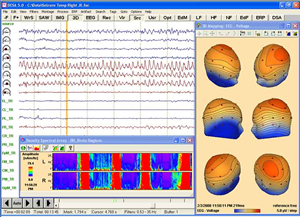

Coregistration of MRI with EEG & MEG

Coregistration of MRI with EEG & MEG

For an easy superposition of the results of source analysis with individual EEG and MEG data, BrainVoyager provides an interactive link to BESA (Brain Electrical Source Analysis). The bidirectional connection of the two programs allows for source seeding from fMRI clusters with one mouse click.